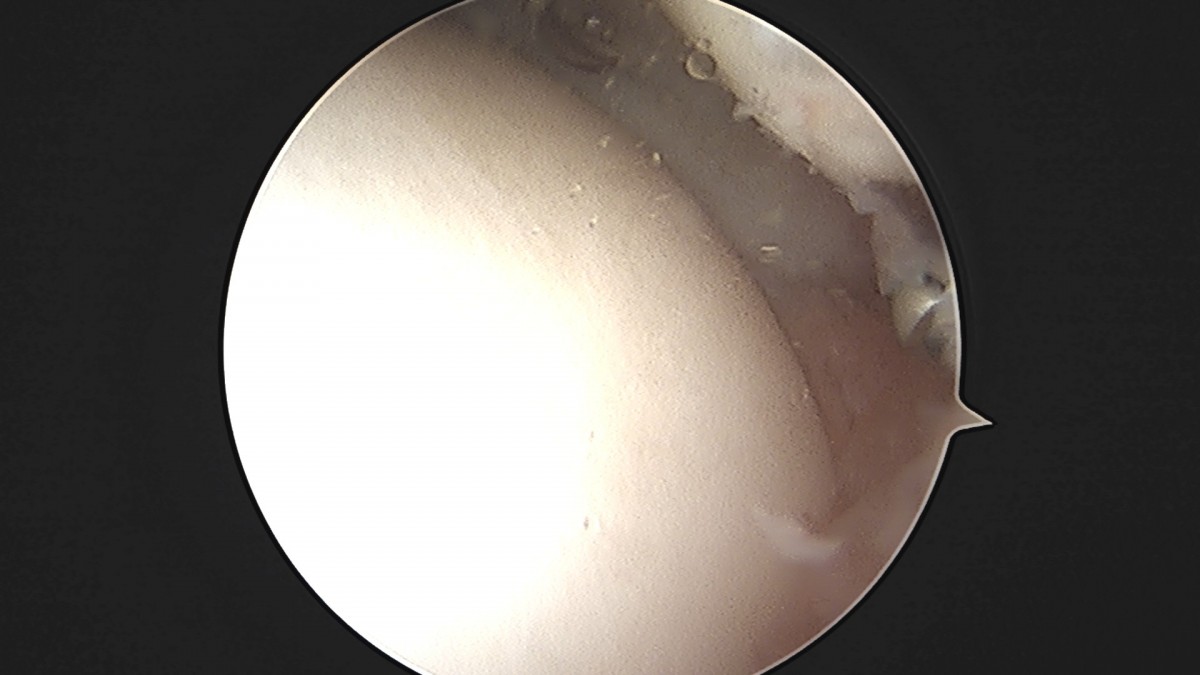

이재상원장님 발목 활액막 절제술 및 인대 봉합술 정보O 환자

dae765e4d9ac96aee867c9d6292d8784_1758003797_7751.jpg